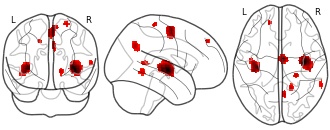

"name": "Multi_VBMsmaller_fMRIdecreased",

"description": "Multi-modal analysis in BPD. Brain regions exhibiting smaller gray matter and decreased activation during emotion processing in BPD compared to healthy controls. Note: Results were thresholded at p<.0025. Note2: Results were updated (see Erratum for this publication).",